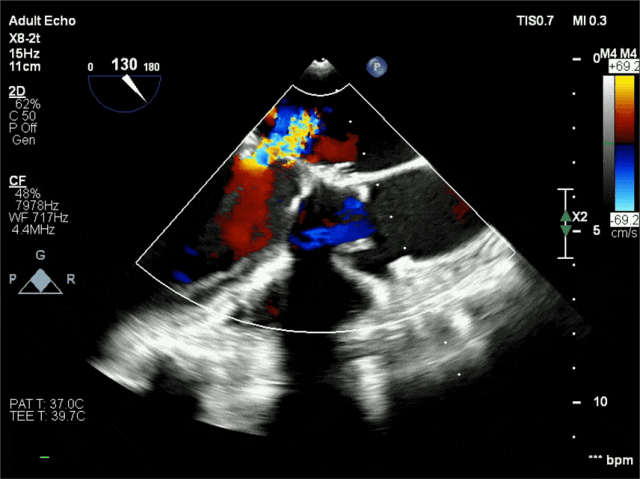

术前超声

超声可见二尖瓣位生物瓣植入状态,瓣架强回声,瓣膜增厚、回声增强,舒张期前向血流速度增快,峰值流速2.4m/s,峰值压差23mmHg,平均压差8mmHg,收缩期后侧脱向左房侧,对合错位,其左房侧可见重度偏心性反流信号。